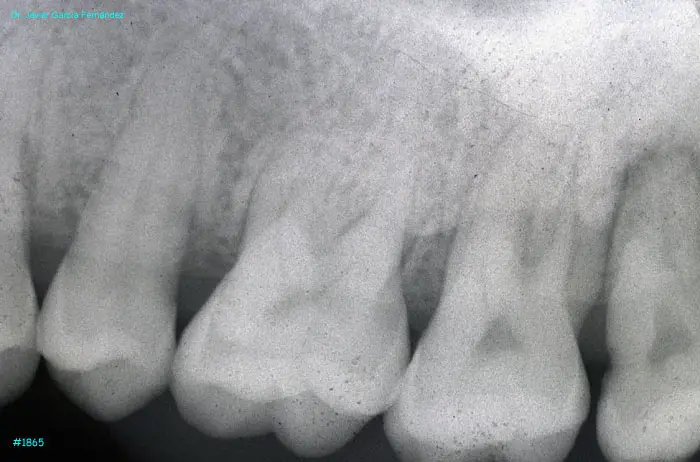

image 16